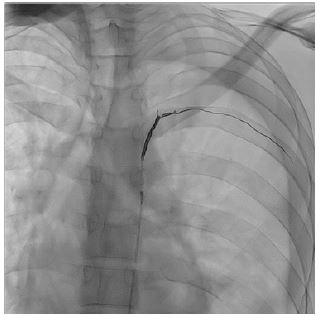

The patient underwent superselective arterial embolization of the involved intercostal artery (Figure 1). The procedure was successfully performed using microcoils (3 and 4 mm), obtaining immediate stop of bleeding (Figure 2). A left chest tube was placed and 1200 mL of blood were evacuated. The patient then underwent videothoracoscopic debridement to evacuate clots and some retained blood.

Figure 2: Successful superselective arterial embolization.